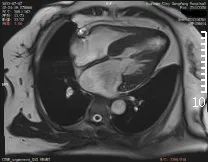

心脏磁共振检查

正式开展心脏磁共振(CMR)检查

是除心脏彩超、冠脉CTA之外的

另一种先进检查技术

具有无X线辐射、任意平面成像的优势

是集形态、灌注、功能及分子成像

于一体的成像技术

心脏磁共振能够对

心肌病、冠心病、先心病

心脏瓣膜病、心包疾病、心脏肿瘤

等病变进行诊断及鉴别诊断

在心脏形态与功能、心肌评估中

具有优势

对淀粉样心肌病、致密化不全心肌病等

具有独特诊断优势

半个月的时间,东方总院

已成功检查和诊断心脏病变3例